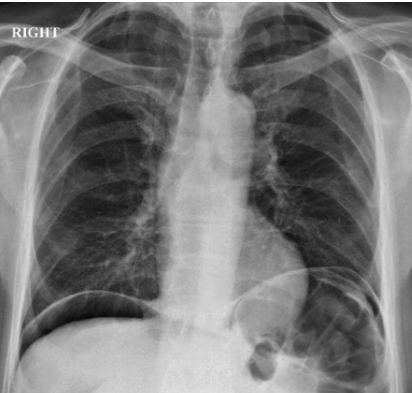

If you saw these X-ray appearances in the setting of acute abdominal pain, what would be the most appropriate course of action?

Resuscitate the patient and inform the surgeons

A large volume of free gas is present under the diaphragm. In the context of acute abdominal pain this finding indicates perforation. Emergency resuscitation and informing the surgeons would be the most appropriate action.